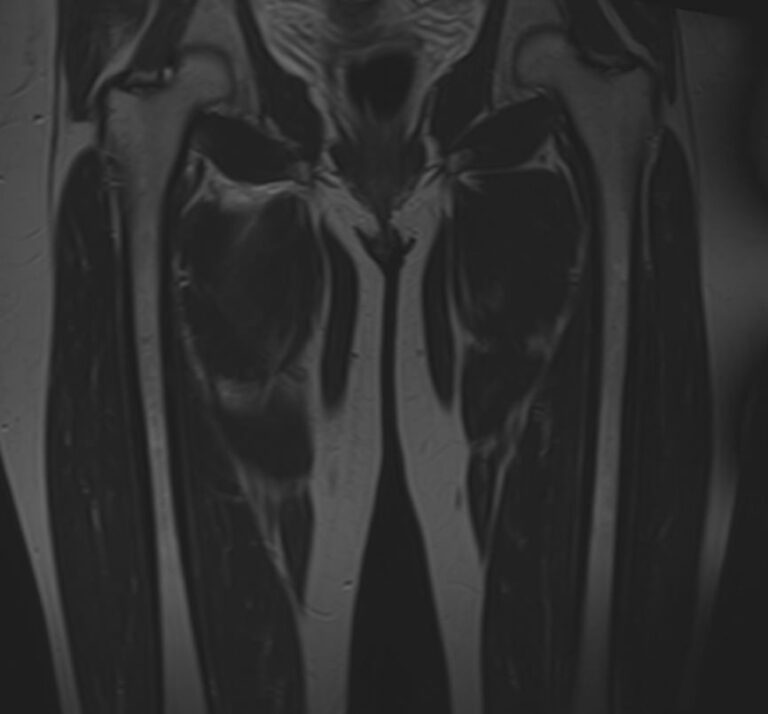

Магнитно-резонансная томография применяется для обследования мягких тканей верхних и нижних конечностей, включая кожу, подкожно-жировую клетчатку, мышцы, фасции, межфасциальные пространства, сухожилия, связки, сосудистую систему, лимфоузлы и лимфатические протоки, нервные волокна, надкостницу и костный мозг.

При проведении МРТ используется действие внешнего магнитного поля без применения вредного рентгеновского излучения, что делает процедуру безопасной для организма человека. Помимо безопасности, достаточной быстроты и неинвазивности метод обеспечивает высокую степень визуализации мягкотканных структур по сравнению с другими исследованиями, например, обычным рентгеном, КТ или УЗИ.

Кроме того, имеет значение показатель индукции магнитного поля томографа. Наша клиника оснащена современным высокопольным томографом последнего поколения TOSHIBA VANTAGE TITAN 1,5 Тесла. Высокая индукция магнитного поля обеспечивает повышенную четкость изображений при обследовании мягких тканей конечностей. За счет послойного сканирования в различных плоскостях с шагом от 1 мм и последующего преобразования данных в объемные изображения томограф обеспечивает выявление мельчайших изменений в тканях. Это позволяет проводить диагностику различных заболеваний на самых ранних стадиях.